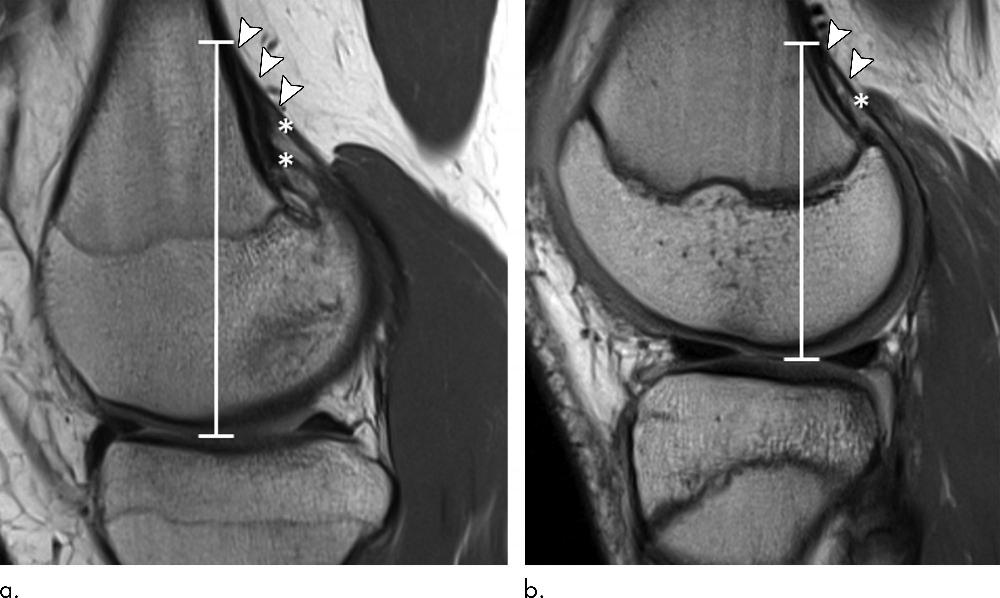

Figure 2. Sagittal proton density–weighted MRI scans in two 15-year-old female control participants without a distal femoral cortical irregularity demonstrate measurement of the tendon attachment position. Images show the craniocaudal position (white line) of the tendon attachment, which is defined as the distance from the level of the joint space to the most cranial attachment of tendon slips (arrowheads) for the (a) medial and (b) lateral head of the gastrocnemius muscle (*). Note that the tendon of the medial gastrocnemius head in a shows two prominent tendon slips.